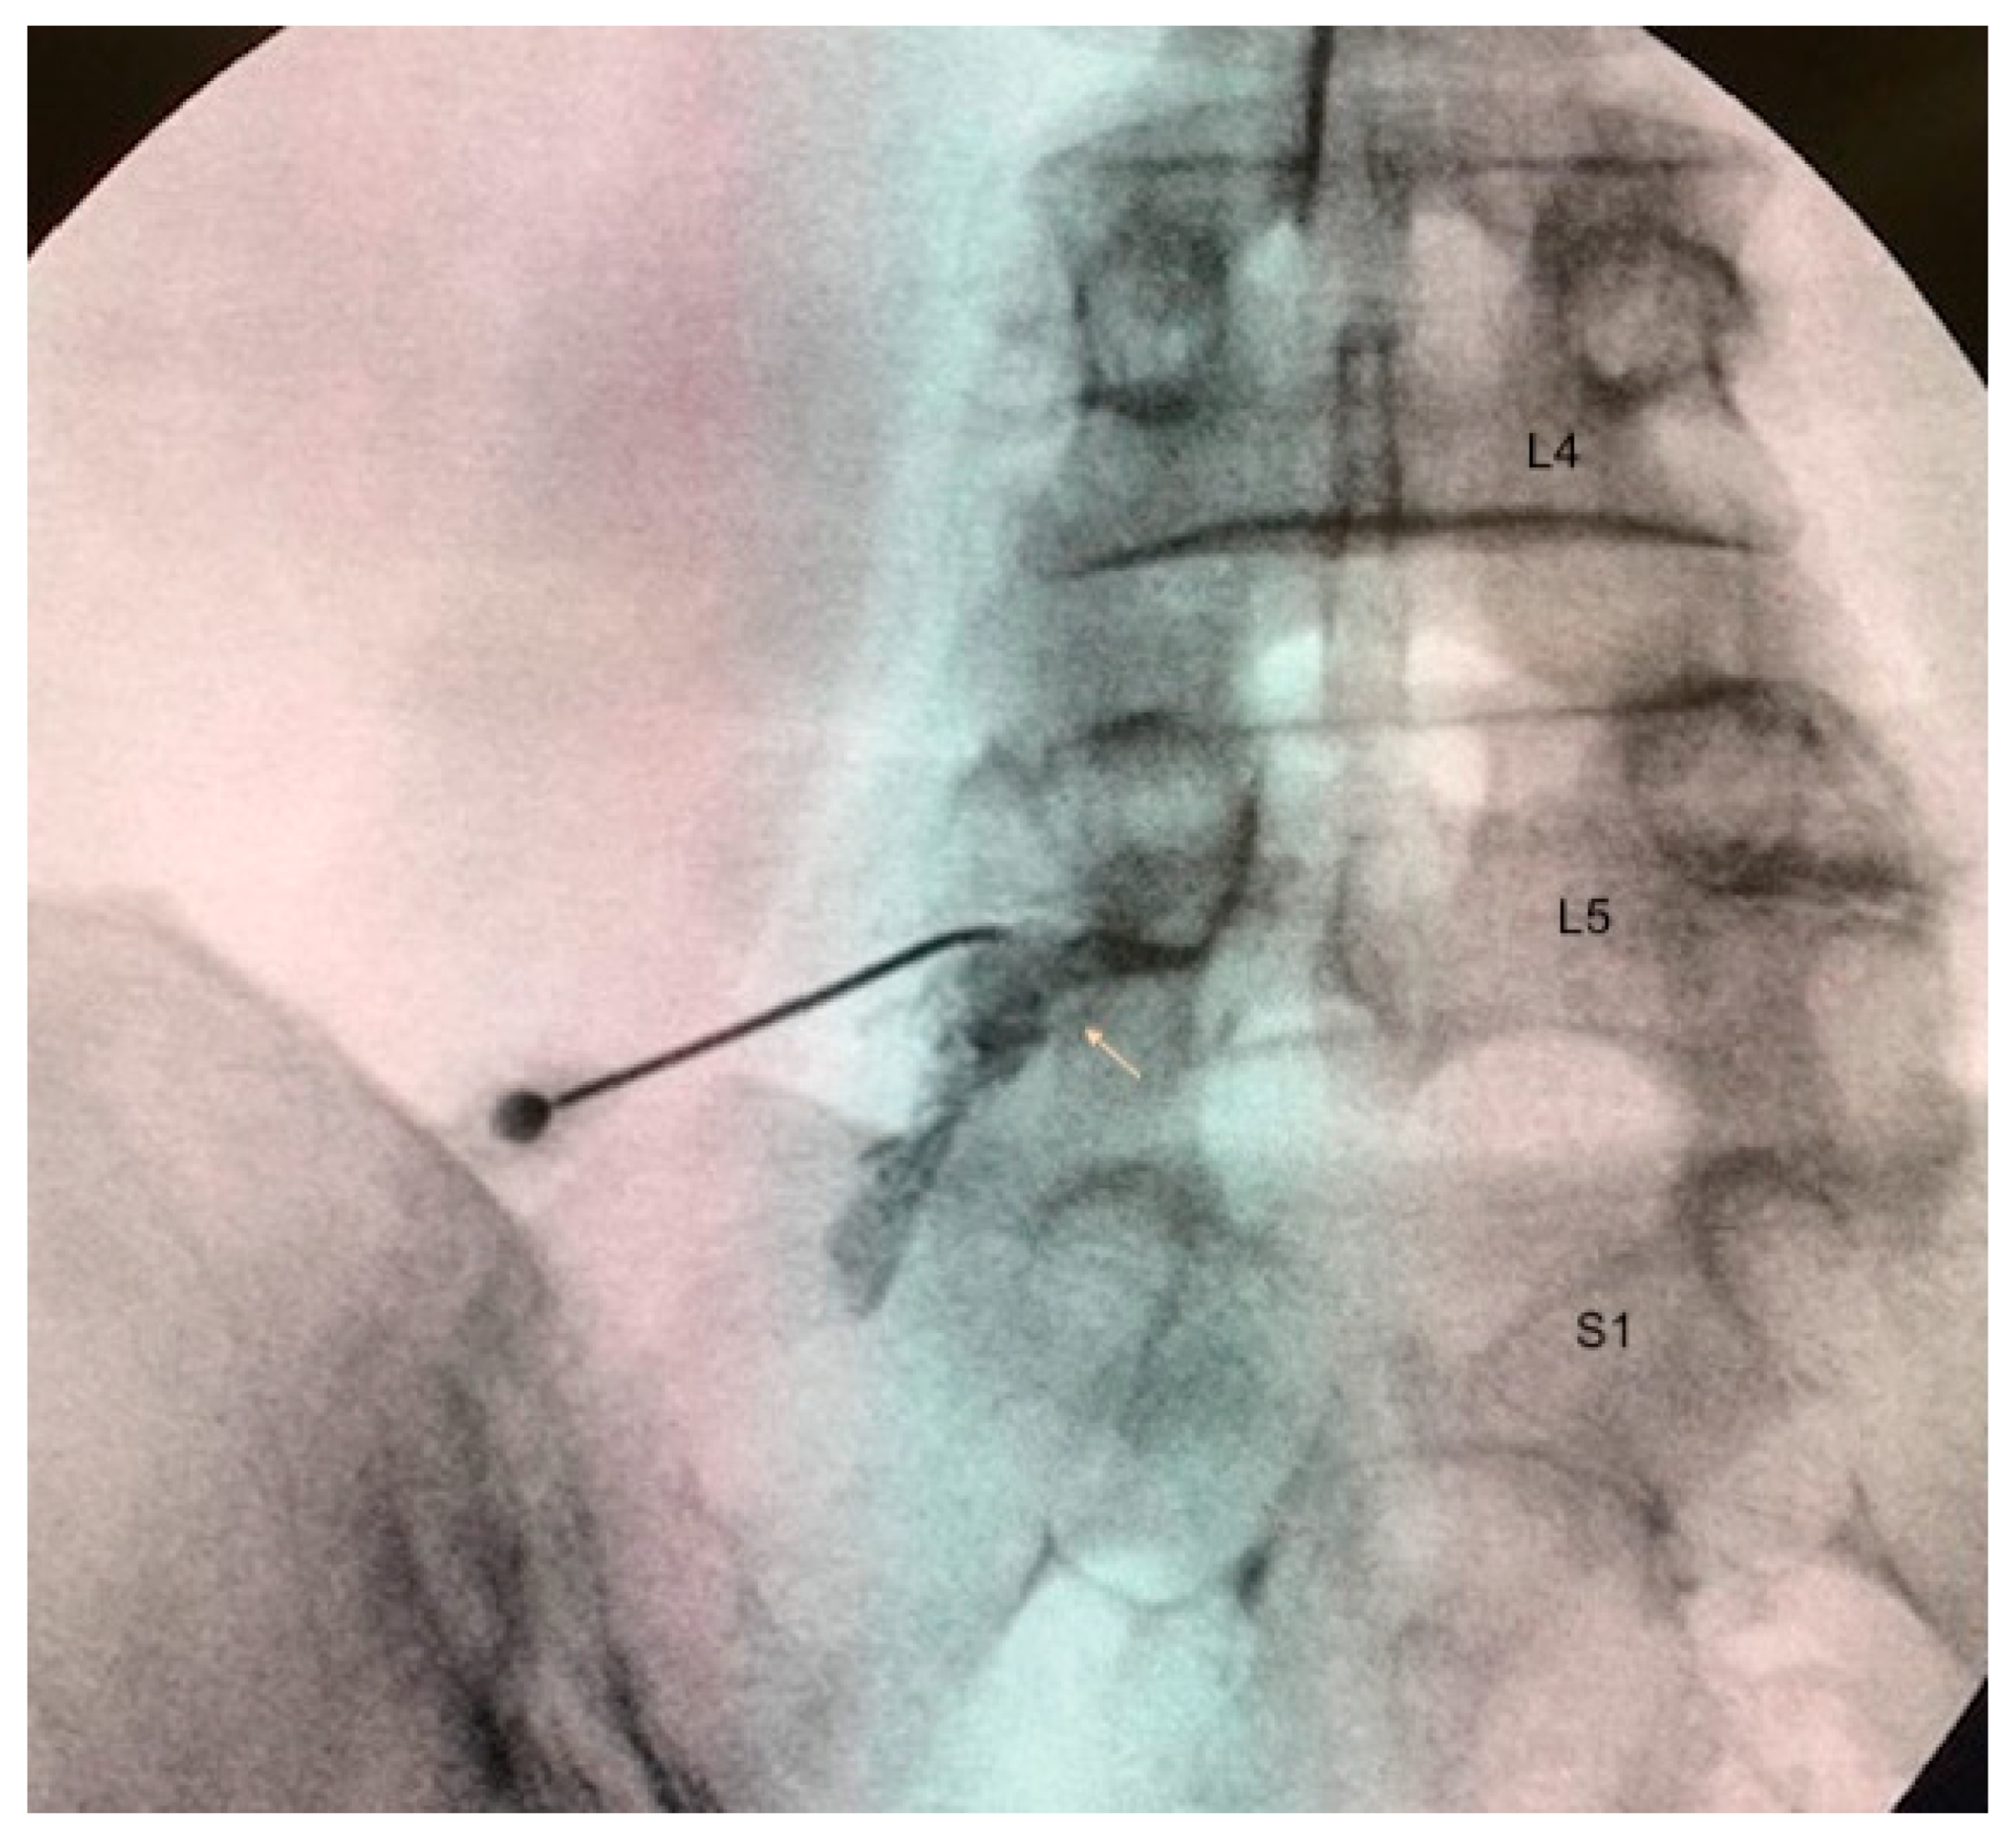

2.4. Treatment Administration